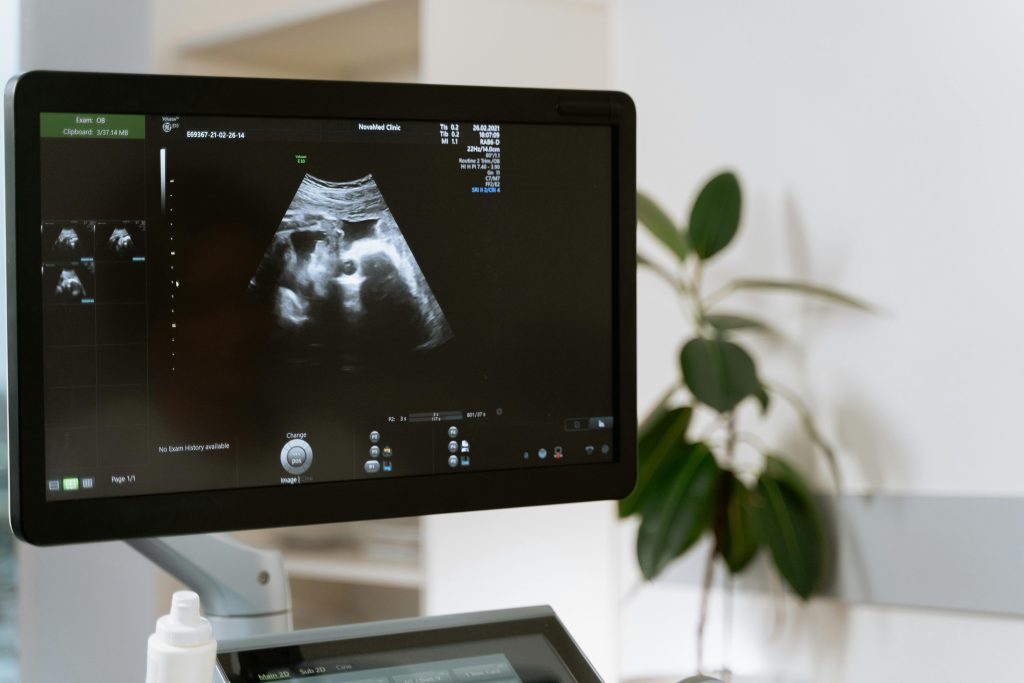

Welke medische echo’s zijn er?

Een vitaliteitsecho wordt gemaakt op medische indicatie tussen de 7 en 9 weken. De echo is bedoeld om te kijken of de zwangerschap intact is, zich in de baarmoeder bevindt en of er geen afwijkingen in en rondom de baarmoeder te zien zijn.

De termijnecho wordt gemaakt om te bepalen hoe lang je al zwanger bent en zo de uitgerekende datum vast te stellen. De termijnecho geeft precies aan hoe oud de ongeboren baby is (dus wanneer de bevruchting plaatsvond).

De 13- en 20 weken echo gaat op dezelfde manier als de meeste andere echo’s tijdens je zwangerschap. De 13 weken echo zijn medische onderzoeken, bij beide onderzoeken kijkt een echoscopiste of je kind lichamelijke afwijkingen heeft.

De 20 weken echo gaat op dezelfde manier als de meeste andere echo’s tijdens je zwangerschap. De 20 weken echo zijn medische onderzoeken, bij beide onderzoeken kijkt een echoscopiste of je kind lichamelijke afwijkingen heeft.

Gedurende de gehele zwangerschap kan er bij vaginaal bloedverlies een echo gemaakt worden om oorzaak te achterhalen en te kijken of de zwangerschap nog intact is.

De groeiecho is een echo om te kijken of de groei van je kindje goed is. Het hoofdje, buikje en bovenbeentje worden gemeten en er wordt gekeken naar de hoeveelheid vruchtwater.

Deze echo wordt rond 34 weken zwangerschap gemaakt om te kijken of de placenta niet voor de baringsuitgang ligt. Hierbij wordt vaak ook inwendig gekeken.

De liggingsecho wordt gemaakt om te kijken waar het hoofdje van het kindje ligt. Meestal wordt deze echo rond 35-36 weken gedaan.